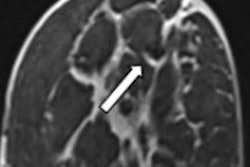

As an example, the researchers noted the results of a 39-year-old patient with hormone receptor-positive, HER2-negative breast cancer. They wrote that while CT at the initial staging of the thorax and abdomen gave suspicion of lymph node infiltration, conventional imaging couldn't clearly represent the tumor-infiltrated lymph node.